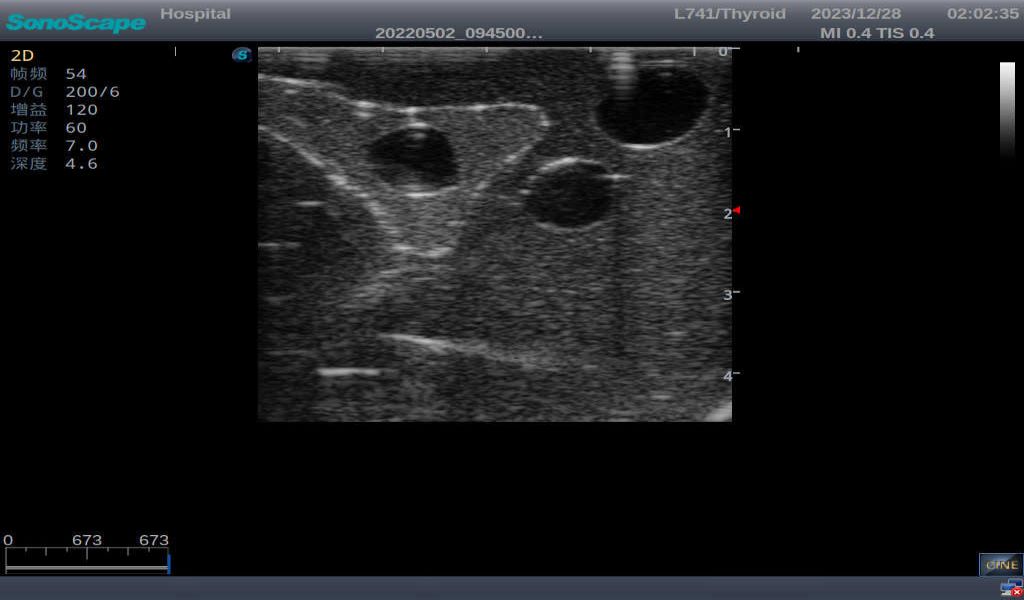

Thyroid Ultrasound Training Model

This product has true-to-life male torso including head, neck, shoulder and upper chest. It serves as an excellent teaching tool for identification of various types of normal thyroid, thyroid adenoma, thyroid cancer, nodular goiter, thyroid cyst and training on proper thyroid scanning techniques.

2)       Ultrasonically realistic materials at neck & various types of real ultrasonic machines in clinical available, developing realistic imaging like common carotid artery, internal jugular vein, trachea, thyroid cartilage, cricoid cartilage, lobes of thyroid gland and isthmus

3)       It comes with four (4) thyroid modules and can show five (5) ultrasonic images: normal thyroid, thyroid adenoma, thyroid cancer, nodular goiter, thyroid cyst

Thyroid cyst, which fluid area, dark and echo-free area can be seen